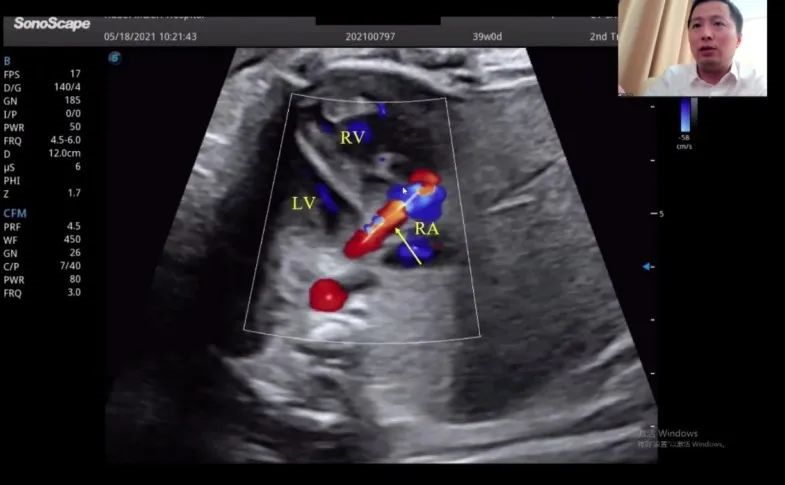

浙江大學(xué)醫(yī)學(xué)院附屬邵逸夫醫(yī)院的趙博文教授聚焦先天性心臟疾病(CHD)的產(chǎn)前診斷,通過特殊病例的展示講解,包括法洛四聯(lián)癥(TOF,一種常見的先天性心臟畸形)的時(shí)空關(guān)聯(lián)成像技術(shù)(Spatio-Temporal Image Correlation,STIC)、大動(dòng)脈完全轉(zhuǎn)位(cTGA)和右心室雙出口(DORV)的圖像,前瞻性地提出智能胎心的應(yīng)用場景。“胎心檢查人工智能的應(yīng)用非常有價(jià)值,能夠縮短檢查時(shí)間,提高臨床的診療效率,”趙教授如是說。

湖北省婦幼保健院的趙勝教授在會上帶來了胎兒冠狀動(dòng)脈瘺超聲診斷研究的分享。趙教授表示,冠狀動(dòng)脈瘺在妊娠晚期可通過超聲檢查顯示出來,經(jīng)線圈栓塞或冠狀動(dòng)脈瘺術(shù)后,進(jìn)一步的臨床過程通常較為順利。